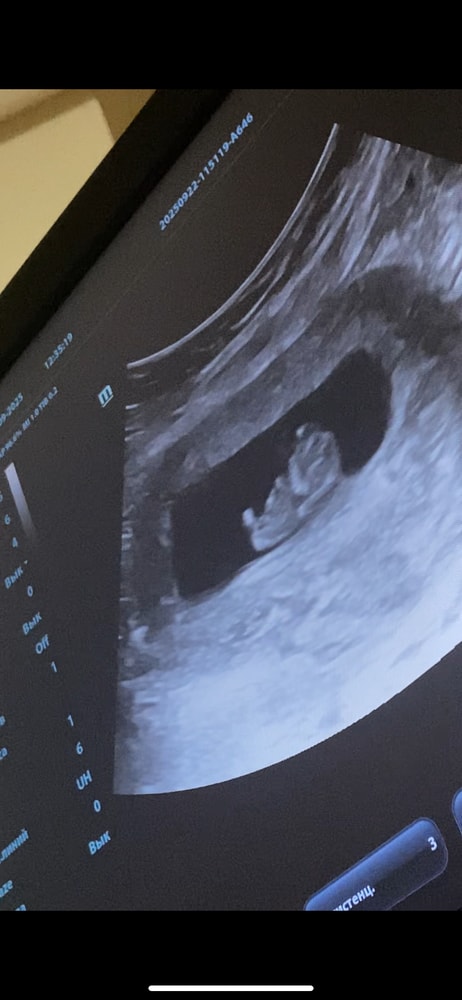

Моя креветка ❤️

Изображение

22.09.2025

Ой... У меня тоже малыш по передней стенке.... Очень переживаю как там плацента, ведь у меня тоже шов от кесарева... Завтра иду на первый скрининг

Мария, у меня прямо на швах ( но врач говорит должна подняться 🤞🏼🤞🏼🤞🏼